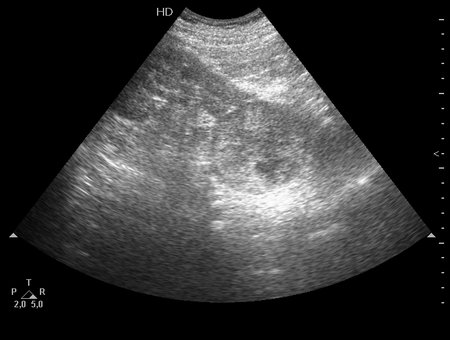

Опухоль почки. Renal tumor.

Мужчина средних лет. Жалоб нет.

Гистология - RCC.